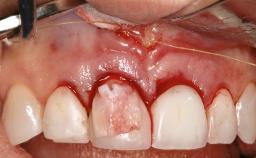

In this case, Myroslav Solonko, Ignacio Sanz Sánchez and Mariano Sanz present a treatment that aims to eliminate exposed implant threads by modifying the implant surface, converting a moderately-rough surface into a smooth surface.

A 63-year-old male patient was referred to the post-graduate periodontal clinic of the Complutense University of Madrid for the treatment of peri-implantitis. According to the patient’s record, all his maxillary teeth had been extracted ten years previously due to severe periodontitis, and a full-mouth implant-supported restoration on eight implants was placed. No supportive periodontal therapy was provided apart from occasional check-ups by the restorative dentist.